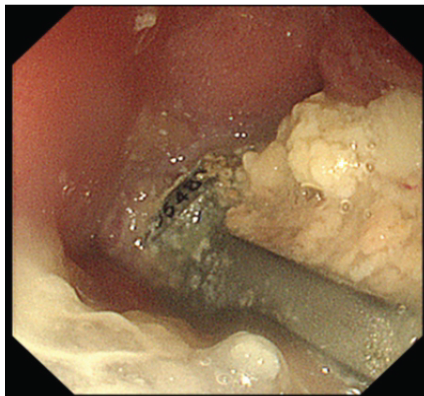

Despite this, his neurological function improved, allowing him to resume independent activities, including recreational baseball. He subsequently stopped attending follow-up visits. At 76 years of age, he returned to the previous hospital with progressive sputum production, worsening limb numbness and weakness, and gait disturbance. Physiological and neurological evaluation revealed bilateral lower-extremity weakness (manual muscle testing: digit extensor 4/4, iliopsoas muscle 3/2, quadriceps muscle 4/4, tibia anterior muscle 5/3, and extensor hallucis longus muscle 4/2), heightened patellar and Achilles tendon reflexes, and dysphagia. His cervical Japanese Orthopaedic Association (JOA) score was 6.5. Radiographs and computed tomography demonstrated vertebral osteolysis around the implant, absence of the right C6 screw, and air between the anterior implant surface and the esophagus (Fig. 2). Magnetic resonance imaging revealed a high-signal lesion from C5 to C7 on short tau inversion recovery sequences with spinal cord compression (Fig. 3). Upper gastrointestinal endoscopy revealed a 2-cm esophageal mucosal perforation with direct exposure of the cervical implant (Fig. 4).

Figure 4: Upper gastrointestinal endoscopic findings. Endoscopy reveals exposure of the anterior cervical plate through a 2-cm defect in the posterior esophageal wall.